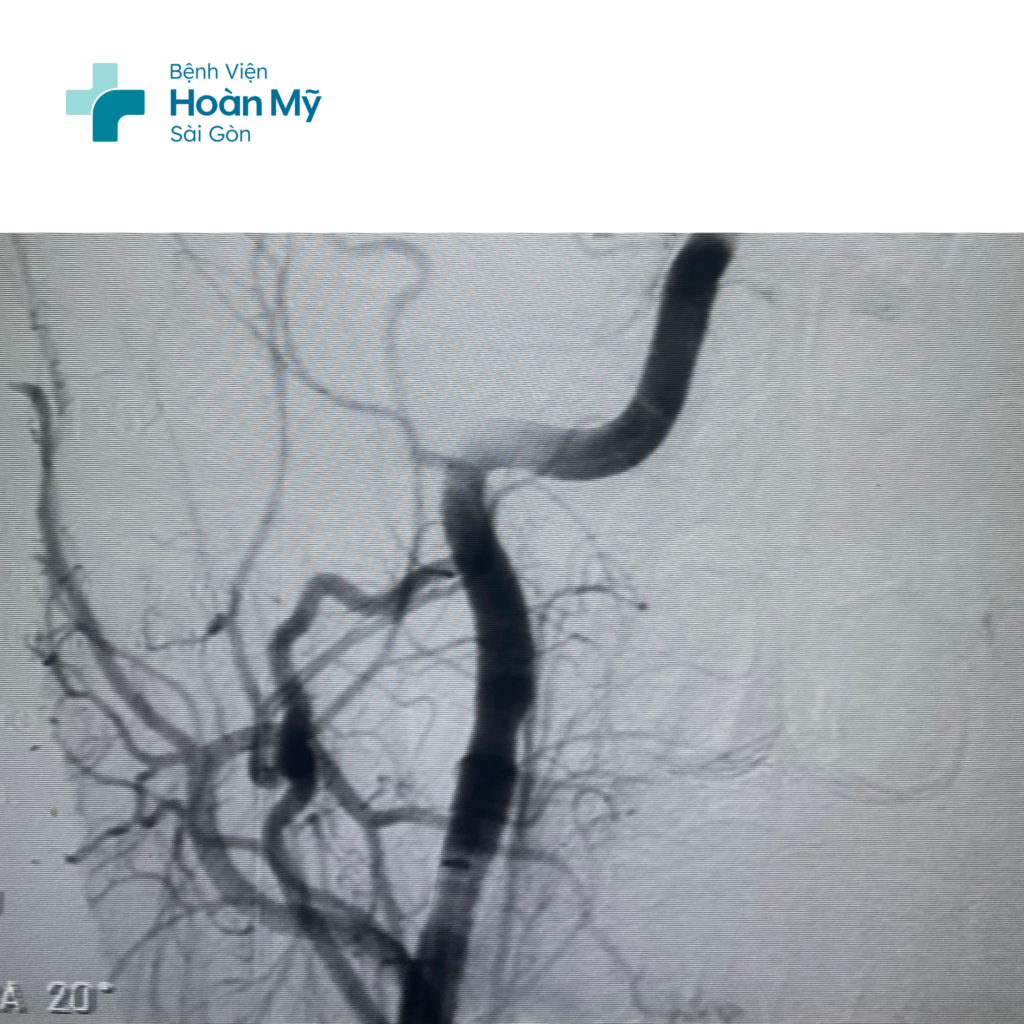

Hình ảnh CT mạch máu não trước can thiệp: Tắc hoàn toàn ĐM cảnh trong và não giữa phải

Hình ảnh ĐM cảnh trong và não giữa phải trước (trái) và sau khi can thiệp (phải)